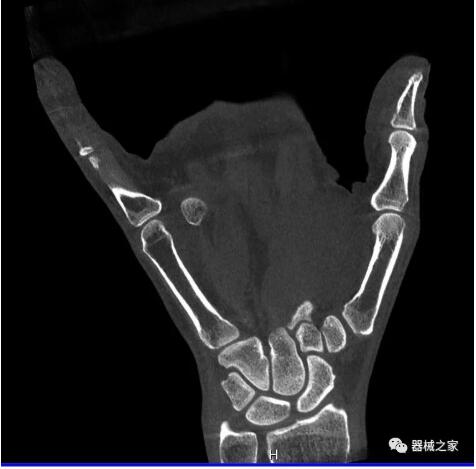

以下是這些“特立獨行”的CT所拍出來的圖像: